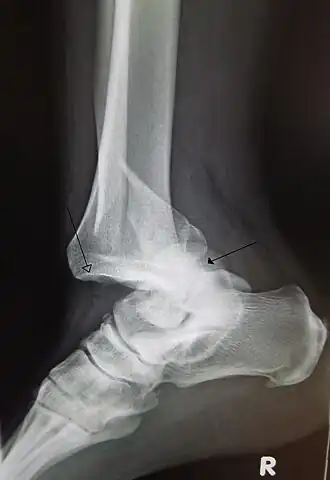

Luxation de la cheville et du pied

La luxation « pure » de la cheville, c'est-à-dire tibio-talaire, est rare, le plus souvent il s'agit d'une fracture-luxation, c'est-à-dire de fractures des extrémités inférieures du tibia ou de la fibula autorisant le déplacement du pied en arrière, en avant ou sur les côtés. La réduction doit être obtenue rapidement, la stabilisation des fractures se faisant secondairement. La luxation peut se produire sous le talus et entraine fréquemment des séquelles. Le talus peut être « énucléé » avec issue de l'os à travers la peau, c'est un exemple de luxation ouverte. Les luxations entre tarse et métatarsiens doivent être réduites au bloc et stabilisées. Les luxations métatarso-phalangiennes suivent les mêmes principes qu'à la main. Les luxations entre les phalanges d'orteils ne posent en général pas de problèmes.